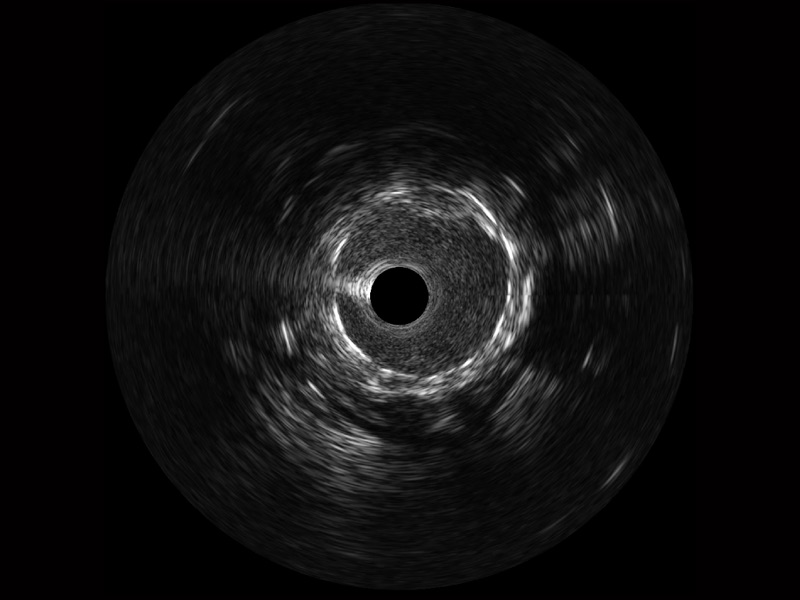

环球UG官网宽频IVUS图像

对比传统IVUS导管成像,环球UG官网宽频IVUS图像的近场支架梁显影更细腻,远场中膜外血管仍清晰可辨,兼顾远中近,兼顾分辨力与穿透深度